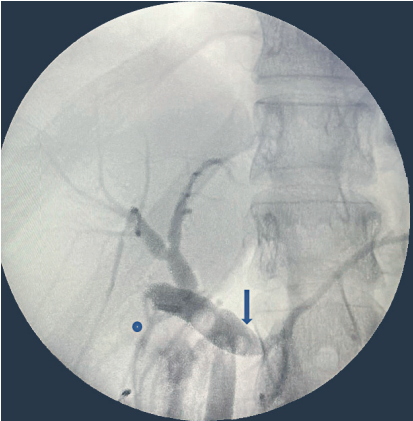

Se presentó el caso en junta multidisciplinaria y por la anatomía no clara se decidió realizar colangio pancreatografía retrograda endoscópica (CPRE) con fin diagnóstico. Se identificó una variación anatómica en la cual el conducto cístico drenaba en el conducto pancreático principal, denominada posible vesícula pancreática. Finalmente, se llevó a exploración quirúrgica por laparoscopia, se disecó el hilio hepático logrando ventana de seguridad de Straberg 10, pero con visualización de una estructura tubular de inserción baja al conducto cístico. Al realizar la colangiografía intraoperatoria no se logró aclarar adecuadamente la anatomía de la vía biliar, se identificaron dos conductos biliares distales, sin poder definir su terminación (Figura 3), por lo que se decidió convertir a cirugía abierta dada la complejidad del caso y la duda anatómica.

Se hizo disección circunferencial anterógrada de la vía biliar extrahepática, identificando un conducto colédoco accesorio (Figura 4). Mediante una nueva colangiografía intraoperatoria no fue posible determinar cuál era el conducto principal y cuál el accesorio para resecarlo. Teniendo en cuenta estos hallazgos y el alto riesgo de desarrollar colangiocarcinoma en el futuro por la variante anatómica, la inflamación y el dolor crónico, se decidió resecar los conductos biliares distales y realizar reconstrucción biliopancreática. Se procedió a la colecistectomía, protegiendo el conducto hepático derecho accesorio que terminaba en el cístico; se seccionó el colédoco proximal posterior a la llegada del cístico, con disección caudal del mismo, donde se observó una bifurcación, configurándose una duplicación del colédoco tipo II. La porción distal de ambos colédocos se disecó, seccionó y se cerraron los muñones lo más cercano al páncreas; finalmente se realizó una hepaticoyeyunostomía en Y de Roux. El reporte final de patología informó un conducto colédoco y conducto accesorio con fibrosis e inflamación crónica, sin evidencia de malignidad.